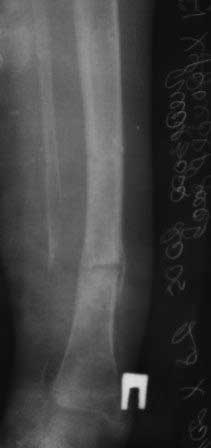

Девочка 2005г.р. В середине 2008 г падает с велосипеда с дедом, возможно был перелом н/з костей левой голени, лечение у знахаря-табиба, но ребенок не смог бегать, часто падал, начал хромать. Май 2009г. обратились к нам, установлен д-з « вялоконсолидирующаяся перелом н/з б/берцовой кости, несросшийся перелом м/берцовой кости со смещением по ширине». Мы решили гипсовая повязка и ходьба с нагрузкой, но по категорическому требованию родителей исправить деформацию м/берцовой кости, произвели операцию ( на свою голову )»о/ репозиция и и/м фиксация спицами м/берцовой кости». Теперь началась самая интересная история! Ч-з недели две в обл. п/о раны м/берцовой открылась свищ с кровянистым выделением, гноя не было, на р-грамме лизис концов отломков м/берцовой кости, к-рый начал прогрессировать, консультирована онкологами, цитология, с подозрением направлена в центральные институты, сделана КТ, онкологическое исключили, в августе попали в остеомиелитический центр, где произведена резекция м/б на протяжение 6-7см, все зажило и выписали (снимок-1). 2010г в мае повторно получила травму, наложена гипсовая повязка (снимок-2) и через 1-2 месяца в одном из центральном институте произведена КДО аппаратом Илизарова , который снят ч-з три месяца (снимок-3) и долго ходила на костылях-мать заставила, как начала наступать, появилась деформация, заказали ортез и так ходила, но деформация прогрессировала, Обратилась к нам в апреле 2012г,(снимок-4) произведена постепенная коррекция на аппарате, и замена на БИОС 01.03.12г плечевым гвоздем, ЭОП нет, поэтому осталась несколько антекурвация (снимок-5), ребенок ч-з неделю начала ходить.Повторный осмотр 22.06.12г- деформация усиливается, за три месяца сращение очень слабое.(снимок-6). (Жаль что многие р-снимки не сохранились, мать обещала хотя бы часть найти)!Что теперь делать?